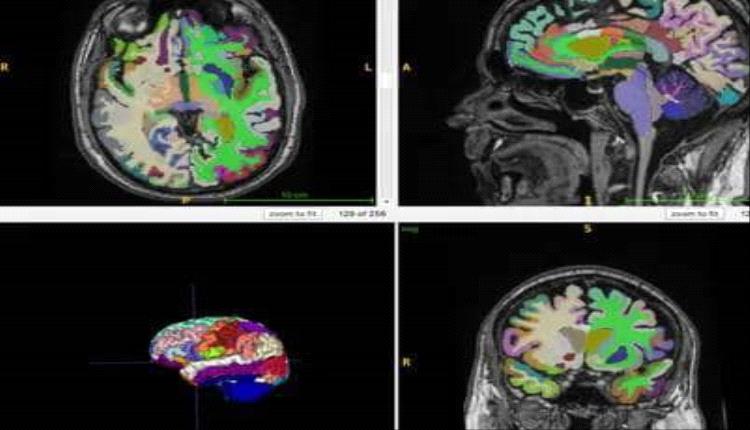

نجح باحثون في جامعة تورو الأمريكية باكتشاف آلية بيولوجية غير مسبوقة تفسر كيفية وصول بعض الهرمونات إلى الدماغ، عبر جسيمات دقيقة في الدم تعرف بالحويصلات خارج الخلوية. وأوضحت الدراسة، المنشورة في دورية Proceedings of the National Academy of Sciences، أن هذه الحويصلات تعمل كناقلات هرمونية، قادرة على تجاوز الحواجز البيولوجية الصعبة مثل الحاجز الدموي الدماغي، ما يفتح آفاقاً جديدة لفهم تأثير الرياضة على الدماغ والصحة النفسية والتوازن الأيضي والاستجابة المناعية.